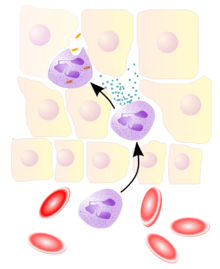

The cellular component involves leukocytes, which normally reside in blood and must move into the inflamed tissue via extravasation to aid in inflammation. Some act as phagocytes, ingesting bacteria, viruses, and cellular debris. Others release enzymatic granules that damage pathogenic invaders. Leukocytes also release inflammatory mediators that develop and maintain the inflammatory response. In general, acute inflammation is mediated by granulocytes, whereas chronic inflammation is mediated by mononuclear cells such as monocytes and lymphocytes.

Leukocyte extravasation

Various leukocytes, particularly neutrophils, are critically involved in the initiation and maintenance of inflammation. These cells must be able to move to the site of injury from their usual location in the blood, therefore mechanisms exist to recruit and direct leukocytes to the appropriate place. The process of leukocyte movement from the blood to the tissues through the blood vessels is known as extravasation, and can be broadly divided up into a number of steps:

- Leukocyte margination and endothelial adhesion: The white blood cells within the vessels which are generally centrally located move peripherally towards the walls of the vessels.[13] Activated macrophages in the tissue release cytokines such as IL-1 and TNFα, which bind to their respective G protein-coupled receptors on the endothelial wall. Signal transduction induces the immediate expression of P-selectin on endothelial cell surfaces. This receptor binds weakly to carbohydrate ligands on the surface of leukocytes and causes them to "roll" along the endothelial surface as bonds are made and broken. Cytokines from injured cells induce the expression of E-selectin on endothelial cells, which functions similarly to P-selectin. Cytokines also induce the expression of integrin ligands such as ICAM-1 and VCAM-1 on endothelial cells, which mediate the adhesion and further slow leukocytes down. These weakly bound leukocytes are free to detach if not activated by chemokines produced in injured tissue. Activation increases the affinity of bound integrin receptors for ICAM-1 and VCAM-1 on the endothelial cell surface, firmly binding the leukocytes to the endothelium.

- Migration across the endothelium, known as transmigration, via the process of diapedesis: Chemokine gradients stimulate the adhered leukocytes to move between adjacent endothelial cells. The endothelial cells retract and the leukocytes pass through the basement membrane into the surrounding tissue using adhesion molecules such as ICAM-1.[13]

- Movement of leukocytes within the tissue via chemotaxis: Leukocytes reaching the tissue interstitium bind to extracellular matrix proteins via expressed integrins and CD44 to prevent them from leaving the site. A variety of molecules behave as chemoattractants, for example, C3a or C5, and cause the leukocytes to move along a chemotactic gradient towards the source of inflammation.